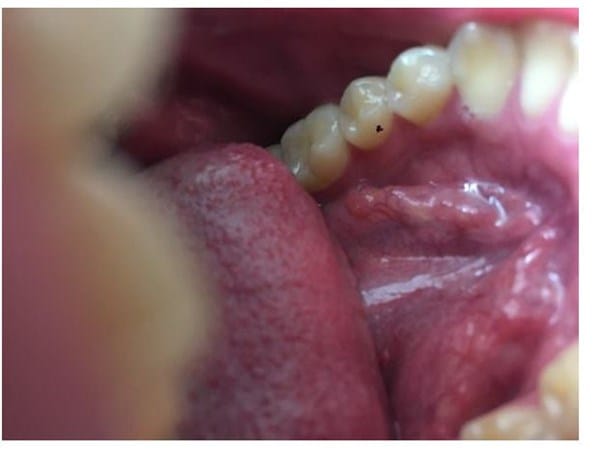

Ampolla roja en el piso de la boca

Hace unos meses tenía una ampolla o roncha o algo medio transparente se veía como si tuviera líquido y hoy me vi la boca y ahora estaba roja como mezclada con sangre y me dio miedo que puede ser? También se siente el sabor a sangre, es que busco en internet y todo lo que me sale es Cáncer de una u otra cosa y tengo miedo. Era una bolita transparentosa que tenía desde el año pasado